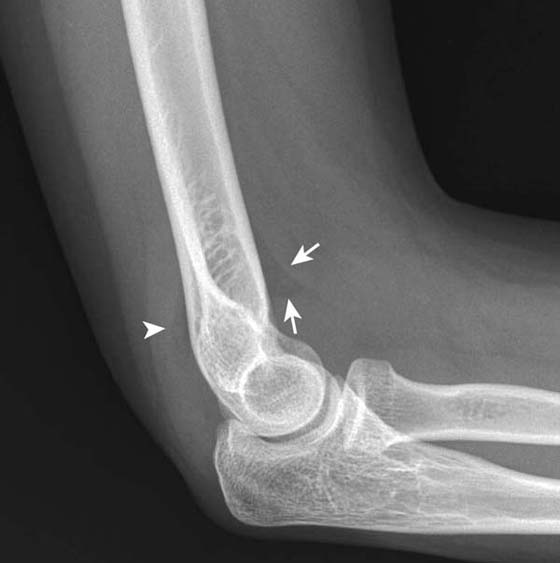

Trauma

Like the shoulder, radiographs are indicated in the assessment of acute trauma at the elbow to determine the presence of fracture or malalignment. A useful sign on lateral radiographs is the visualization of a posterior fat pad or elevation on the anterior fat pad, indicative of elbow joint effusion39 (Fig. 14-15). In the setting of acute trauma the presence of such an effusion suggests an occult radial head fracture. CT is also useful in the setting of complex acute bony injury, facilitating accurate assessment of fracture fragments and degree of displacement before surgical intervention. MRI is of value in the assessment of suggested occult osseous trauma due to its high sensitivity for detection of bone marrow edema and associated fractures. MRI is also warranted where soft tissue injury is suggested, such as in cases of distal biceps tendon or triceps tendon injury.

images

Figure 14-15 Elbow effusion. Lateral radiograph of the elbow shows abnormal elevation of the anterior fat pad forming a “sail” shape (arrows). A faint posterior fat pad is seen (arrowhead). Elevation of the anterior fat pad as shown or the mere visualization of a posterior fat pad indicate an elbow joint effusion. Elbow effusion is often associated with occult fracture with otherwise normal radiographs in the setting of trauma.